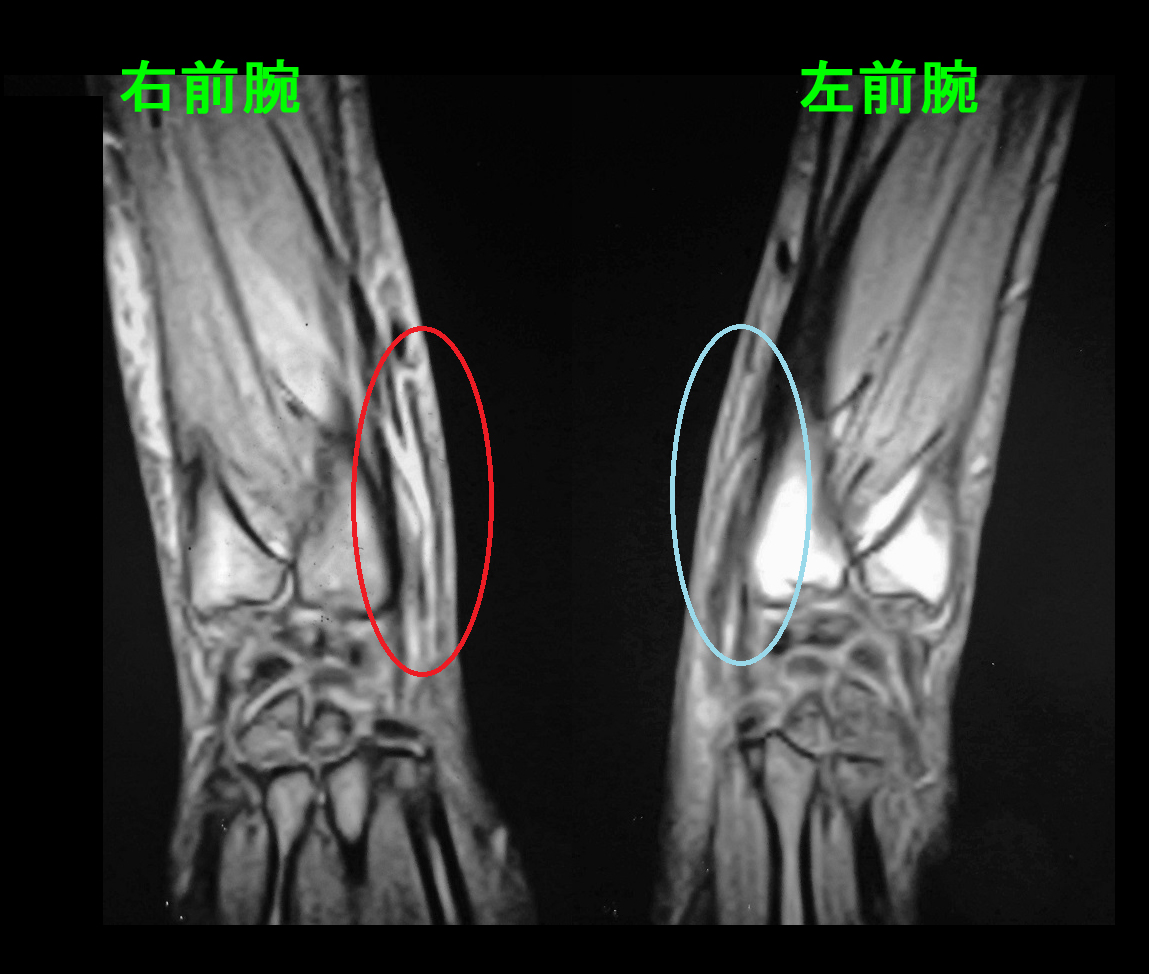

57才男MR1.jpg

MRI所見では前腕遠位(遠位とは体の中心部から遠い位置という意味です)で赤丸領域で黒い腱の周囲が白くなっていて、腱の炎症を示しています。最も皮膚側の黒い腱が母指外転筋腱です。※最初のイラストの腱の構造を参照してください。

MRI所見は57才の男性と同じで、前腕遠位部に手関節伸筋腱周囲は白く炎症所見が確認されます。